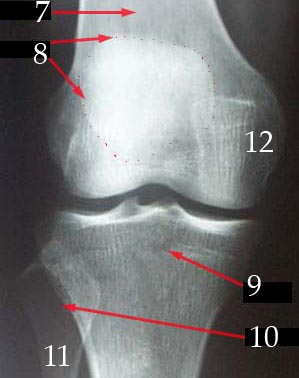

X-Rays

7. Ulna

8. Radius

9. Carpals

10. Metacarpals

11. Proximal Phalanges

12. Middle Phalanges

13. Distal Phalanges

14. Phalanges